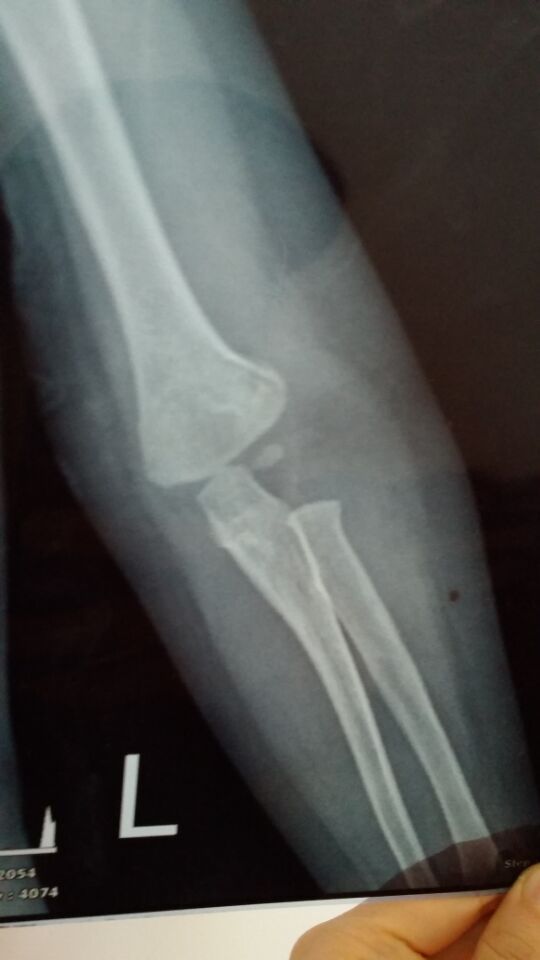

没打石膏是刚摔到拍的 打石膏是今天复查的 请问恢复得好吗?需要打多久石膏?宝宝一岁半 点击展开 匿名用户 2015-07-19 22:49 为您推荐: 其他回答 你好,根据你所描述的情况及提供的片子来看,尺桡骨脱位,行复位后外固定即可。石膏固定1个月左右。 sΰ 2015-07-19 23:23 相关问题 四个月宝宝,半个月复查,医生说再过6天恢复可以就能去石膏了 孩子左肱骨髁上骨折一周后的复查片子,麻烦医生帮我看看恢复的怎么样呢?还有医生为什么把石膏割了一个大 八岁孩子今天上体育课,被其他孩子推了以后,到医院检查,右肱骨髁上骨折,打完石膏回到家,现在不知道要